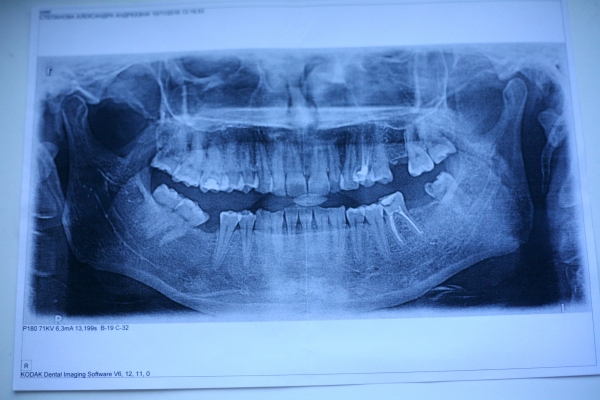

Завтра предстоит удаление нижней восьмерки. Панически боюсь анестезии, а именно онемения горла, щеки, языка. Это самое страшное для меня. В прошлом году удалила семерку - анестезию перенесла нормально. Я бы перенесла удаление на более поздний срок, но через два дня на юг улетать.

Делают ли анестезию без заморозки горла? По ощущениям анестезия для восьмерки такая же, как для семерки или сильнее? Можно ли удалять зуб при температуре 37,1 (простуда)?